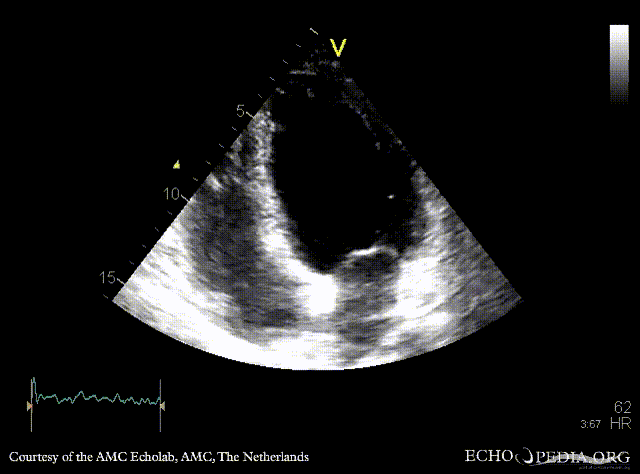

Infarction of posterior and inferior wall

A4CH: akinesia of inferoseptal wall A2CH: akinesia of inferior wall